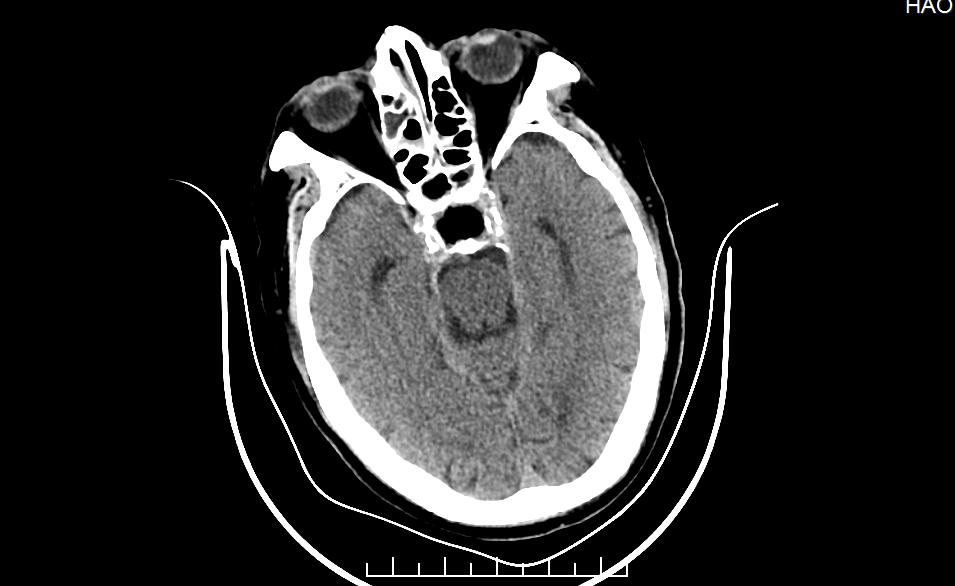

术前MR